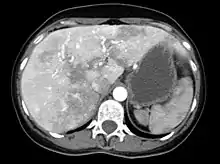

Liver AVMs may be suspected because of abnormal liver function tests in the blood, because the symptoms of heart failure develop, or because of jaundice or other symptoms of liver dysfunction. The most reliable initial screening test is Doppler ultrasonography of the liver; this has a very high sensitivity for identifying vascular lesions in the liver. If necessary, contrast-enhanced CT may be used to further characterize AVMs.[1][2][6] It is extremely common to find incidental nodules on liver scans, most commonly due to focal nodular hyperplasia (FNH), as these are a hundredfold times more common in HHT compared to the general population. FNH is regarded as harmless. Generally, tumor markers and additional imaging modalities are used to differentiate between FNH and malignant tumors of the liver. Liver biopsy is discouraged in people with HHT as the risk of hemorrhage from liver AVMs may be significant.[6][7] Liver scans may be useful if someone is suspected of HHT, but does not meet the criteria (see below) unless liver lesions can be demonstrated.[7]